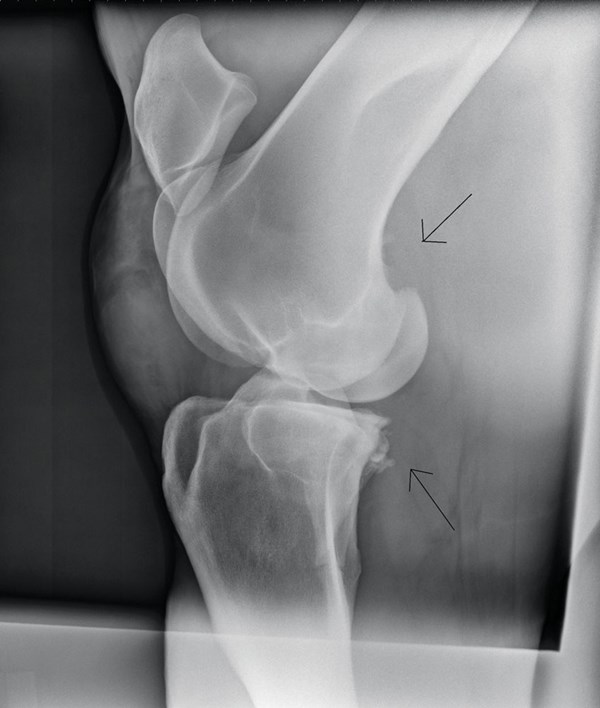

DT-stifle-stress-dressage-horses

Understand Stifle Stresses in Dressage Horses